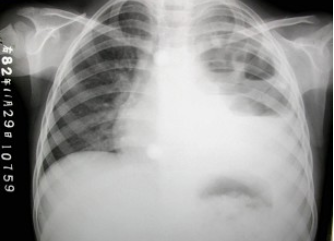

女,8岁,寒战、高热一周,如图所示,最可能的诊断为()

A .左侧肺不张

B .左侧胸腔积液

C .左侧多发性肺脓肿

D .左心室增大

E .以上都不正确